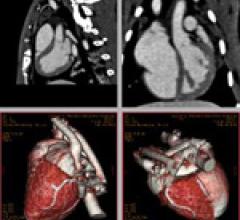

June 12, 2009 – Siemens Healthcare announced the launch of its newest version of Inveon Research Workplace, IRW 3.0, at the 2009 SNM Annual Meeting held June 14-16 in Toronto. This new software provides Inveon users with an expanded set of tools for image visualization and data analysis, and new solutions for important applications in cardiac PET imaging.

June 12, 2009 - NanoScan Imaging LLC today announced the publication of new data demonstrating the use of its investigational, radio-opaque contrast agent (N1177) to visualize vulnerable plaques that can cause heart attack or stroke using advanced, noninvasive and high-resolution computed tomography (CT) techniques.